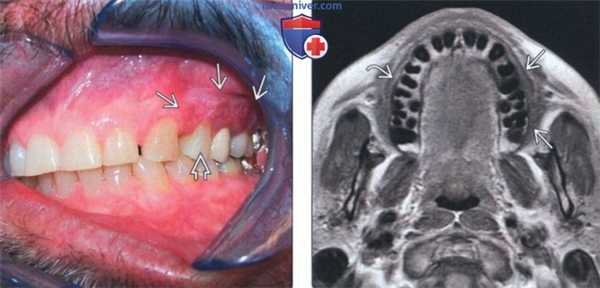

(Слева) На клинической интраоральной фотографии у мужчины 66 лет определяется неровное красное уплотненное и изъязвленное поражение слизистой оболочки щеки в области первого премоляра - моляров слева. При биопсии подтвердился инвазивный ПКР.

(Справа) На аксиальной MPT (Т1 ВИ) у этого же пациента определяется легкое утолщение мягких тканей с наружной стороны альвеолы верхней челюсти. Нормальные жировые пластинки (по сравнению с противоположной стороной) отсутствуют. Убедительных признаков инфильтрации костного мозга на томограммах не выявлено.